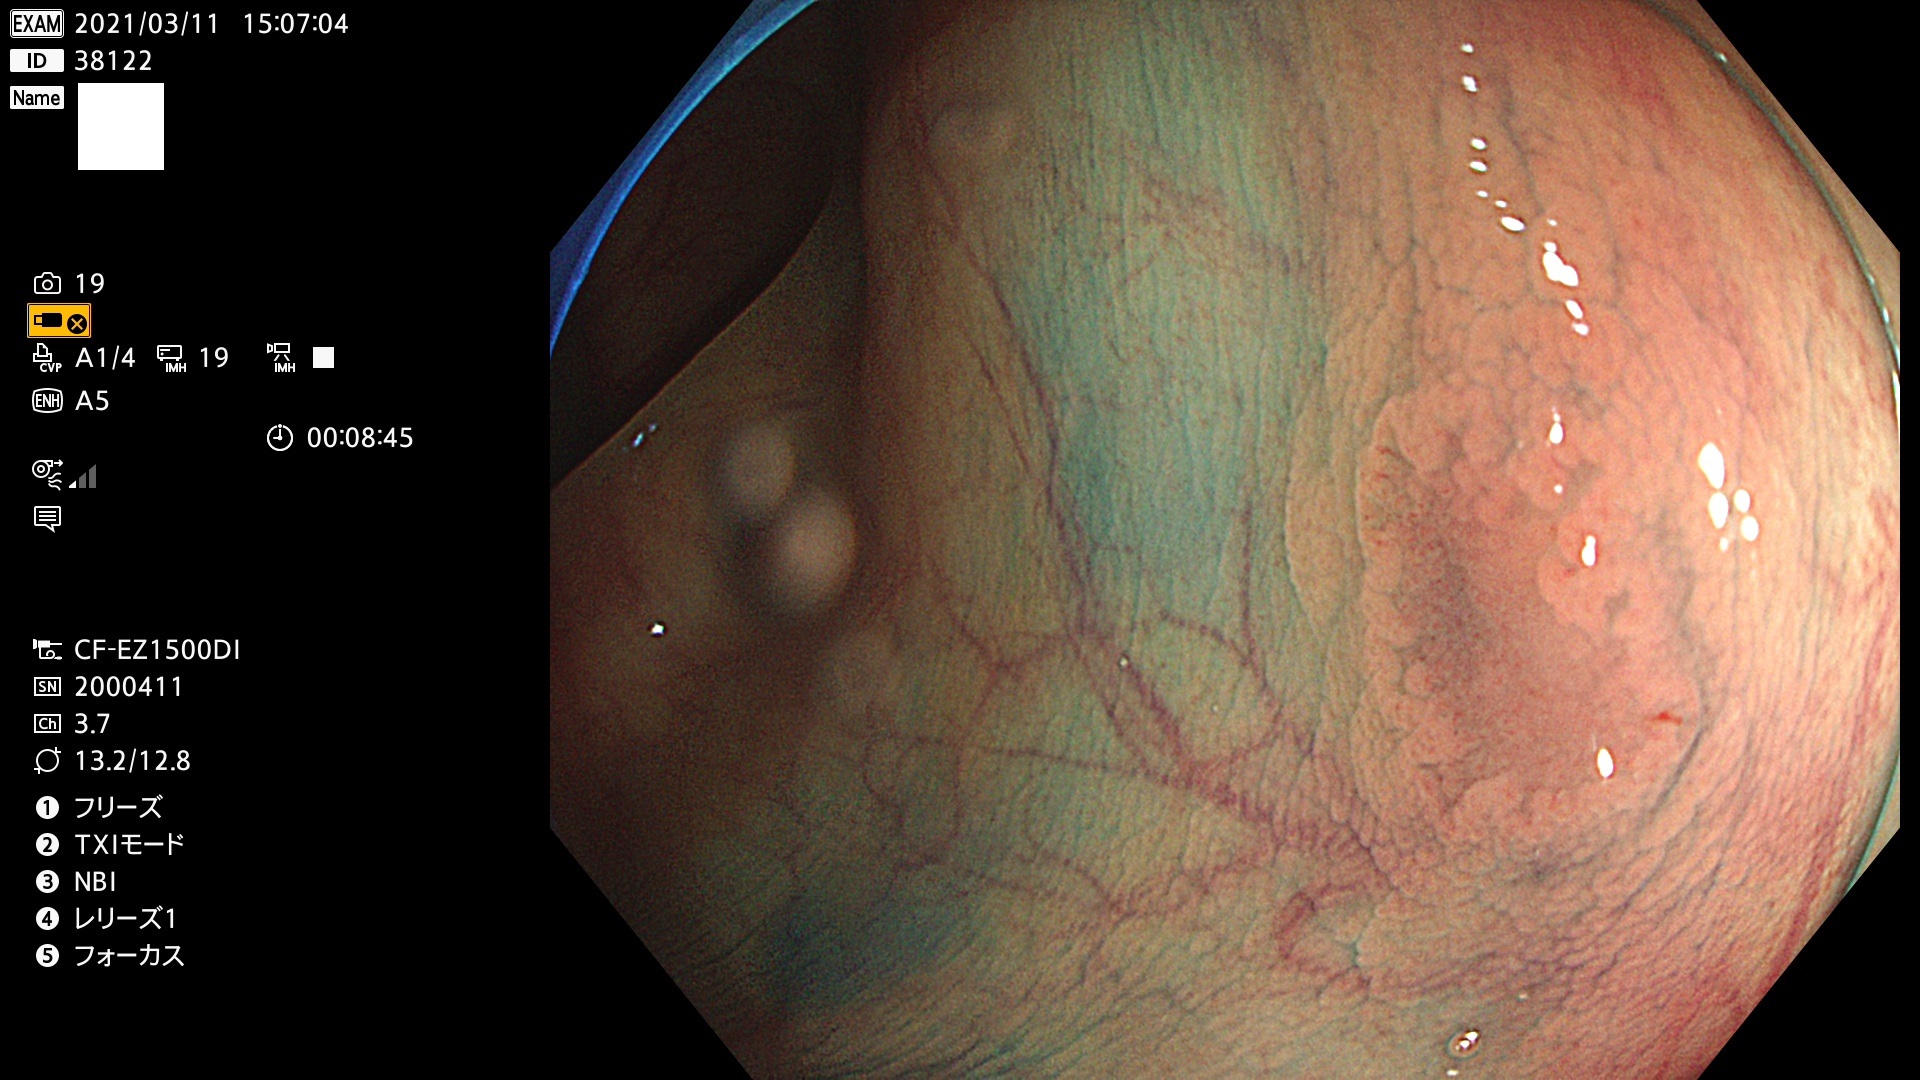

腺腫発見率 72 % (カルテ番号 38100〜38199の100名の方の検査結果で集計)大腸癌検診最新情報

以下のカルテ番号の方に腺腫(Adenoma,Group3〜5)が見つかりました(集計法)

38101 38103 38104 38106 38107 38108 38109 38110 38111 38112 38113 38114 38115 38117 38118 38122 38123 38124 38125 38126 38127 38128 38130 38131 38132 38135 38137 38138 38140 38141 38142(SSAPのみ) 38143 38144 38145 38146 38147 38148 38149 38150 38151 38152 38153 38154 38157 38158 38160 38161 38162 38164 38165 38166 38167 38168 38169 38172 38176 38177 38178 38181 38182 38183 38184 38187 38189 38190 38191 38192 38193 38194 38195 38196(SSAPのみ) 38198

発見困難で危険性の高い平坦型病変(上記100名より抽出) ![]()